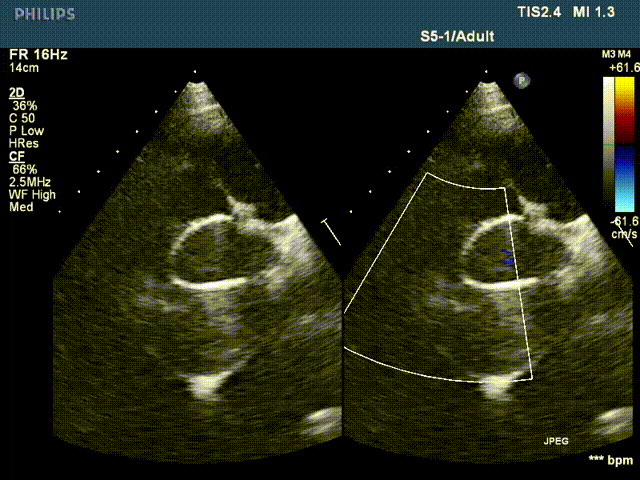

患者李某某,男,61岁,现病史:高血压15年,15年前行主动脉瓣置换术,13年前行升主动脉置换术、冠状动脉旁路移植术。主因心脏瓣膜术后15年,突发胸闷气短20天入院。检查提示:主动脉夹层动脉瘤,主动脉瓣位机械瓣位置、动度未见异常,升主动脉位人工血管上段吻合口漏,原有升主动脉管壁与人工血管之间液区,向右房分流,肺动脉高压(收缩压约51mmHg)。EDV: 192ml, ESV:102ml, FS:23%, SV:89ml。